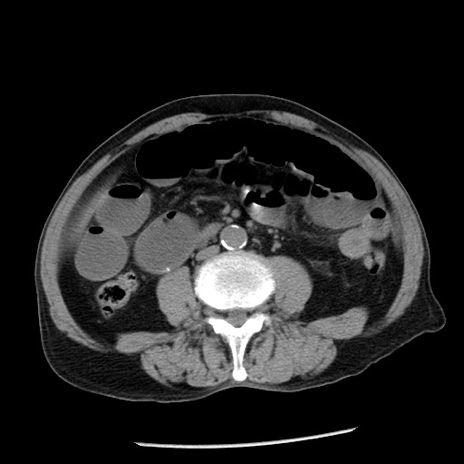

冠状断像

【症例】80歳代男性

【主訴】嘔吐

【現病歴】昨晩2回嘔吐あり、今朝になっても嘔吐あり。来院。

【既往歴】胃潰瘍

【身体所見】意識清明、BT 37.6℃、BP 166/95mmHg、HR 100bpm、SpO2 97%、腹部:平坦・軟、腸蠕動音聴取良好、圧痛なし。

【データ】WBC 21900、CRP 1.46